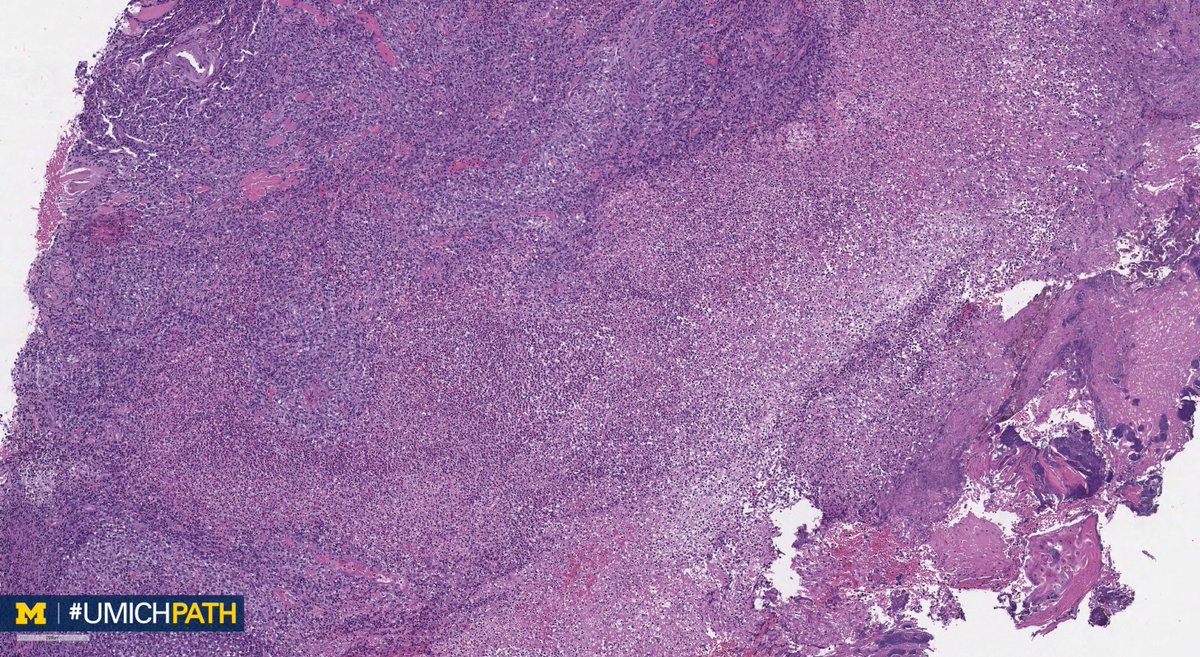

🔬#GYNPath, Day 4. ➡️What’s your #DailyDx of this uterine mass? ➡️What immunohistochemical stain would you order? ➡️We’ll tweet the answer, some quick facts, and the next case tomorrow! #UMichPath

➡️What’s your #DailyDx of this uterine mass?

➡️What immunohistochemical stain would you order?

➡️We’ll tweet the answer, some quick facts, and the next case tomorrow! #UMichPath

A: PEComa. A rare tumor with perivascular epithelioid cell differentiation. Aggressive behavior predicted by size >5 cm, infiltrative growth, hypercellularity, mits (>1/50 HPF), high-grade nuclei, and necrosis. IHC: Positive for sm. muscle & melanocytic markers. #GYNPath #DailyDx

UMichPath's tweet image. A: PEComa. A rare tumor with perivascular epithelioid cell differentiation. Aggressive behavior predicted by size >5 cm, infiltrative growth, hypercellularity, mits (>1/50 HPF), high-grade nuclei, and necrosis. IHC: Positive for sm. muscle & melanocytic markers. #GYNPath #DailyDx